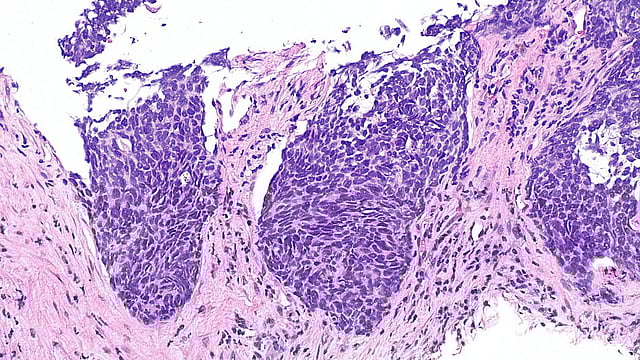

Micrograph showing a non-small cell lung cancer (NSCLC), H&E stain. Wikimedia Commons